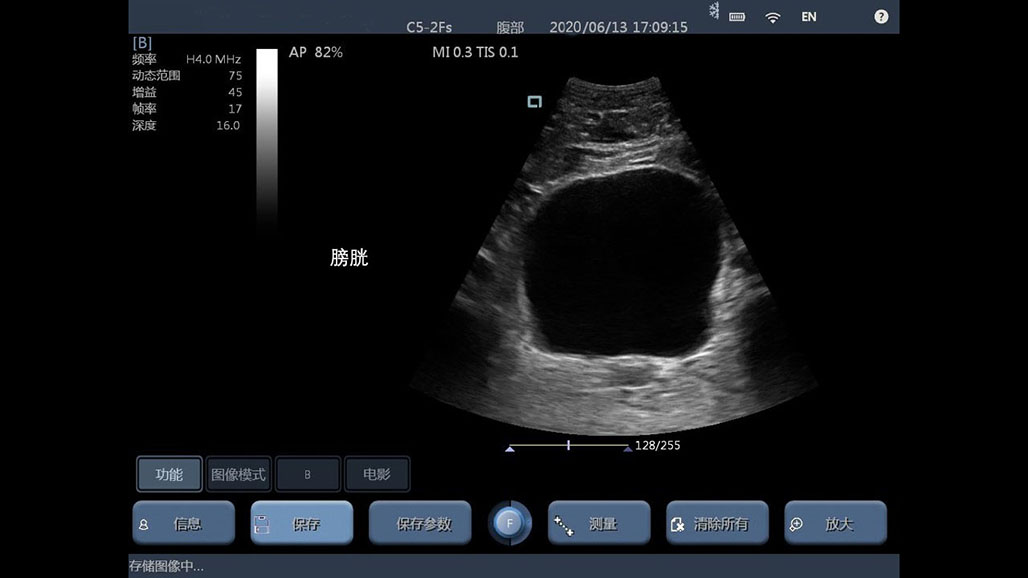

腹部